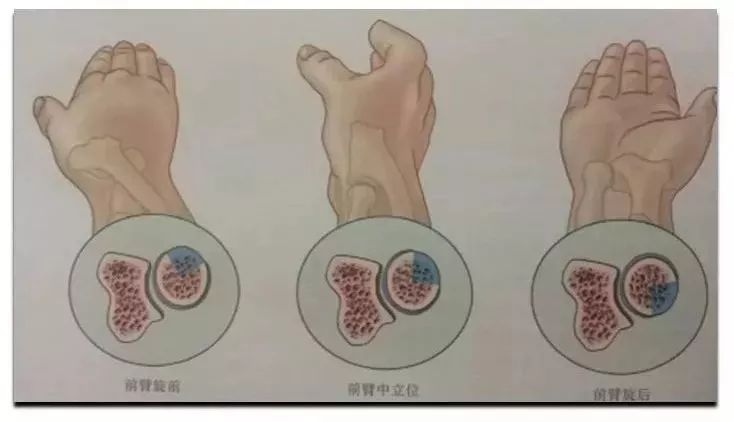

手舟骨骨折 該怎麼辦 科普 每日頭條

技術 腕關節手術入路解析 全球康復資訊 微文庫

手舟骨骨折分型及治療 骨科基礎 骨今中外 微文庫

手舟骨骨折分型及治療 骨科基礎 骨今中外 微文庫

手舟骨骨折分型及治療 骨科基礎 骨今中外 微文庫

橈骨遠端骨折詳細解析與方法提供 及相應個人見解 每日頭條

橈骨遠端骨折詳細解析與方法提供 及相應個人見解 每日頭條

橈骨遠端骨折詳細解析與方法提供 及相應個人見解 每日頭條

橈骨遠端骨折詳細解析與方法提供 及相應個人見解 每日頭條